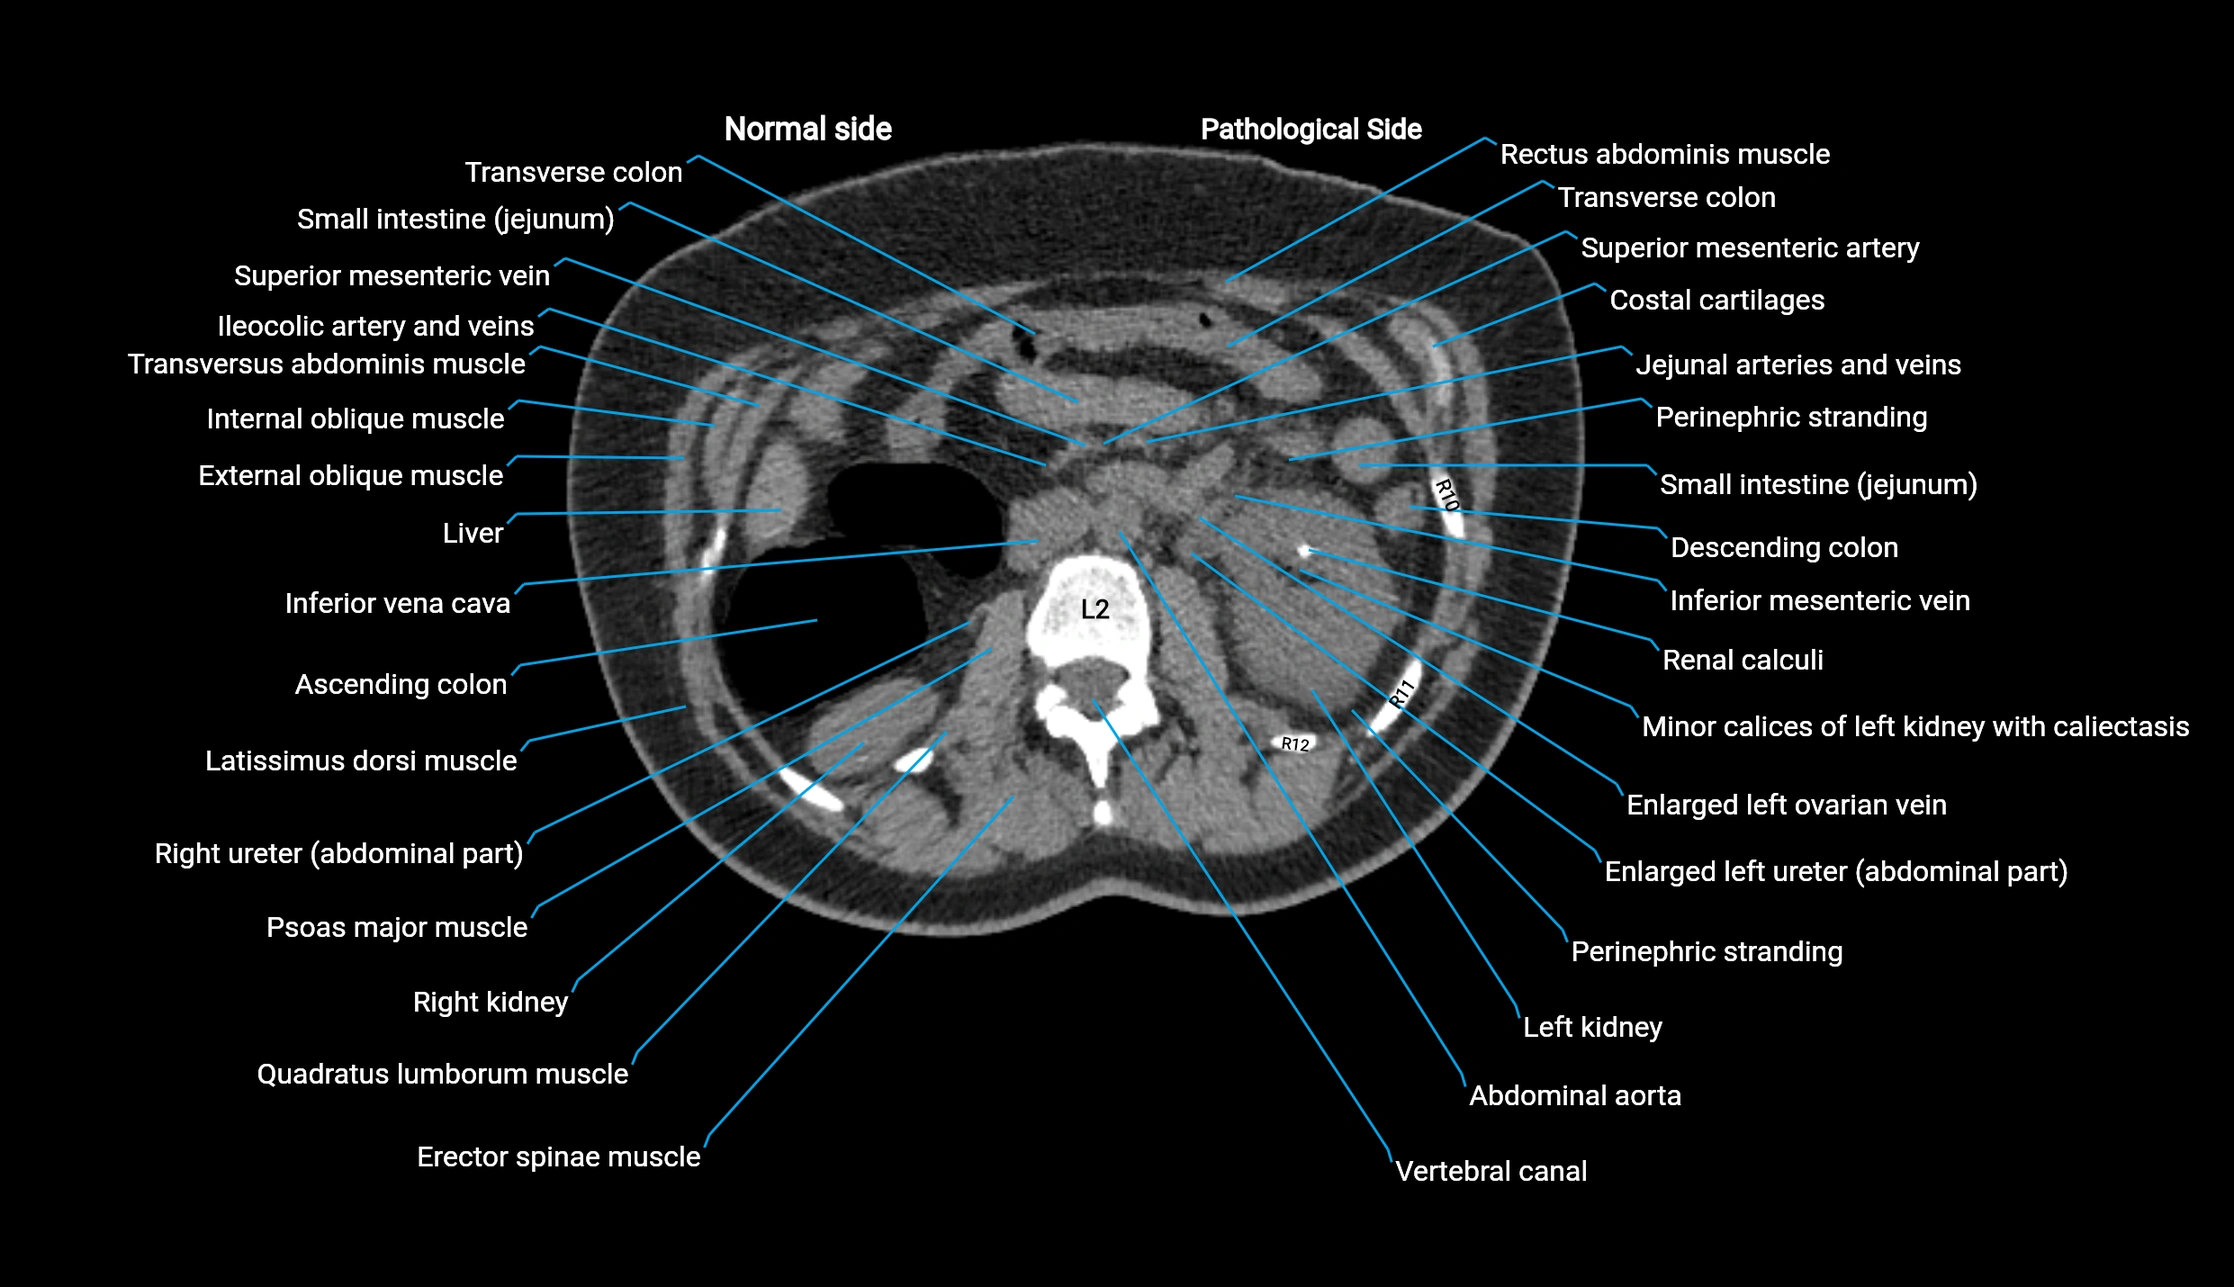

CT image

image